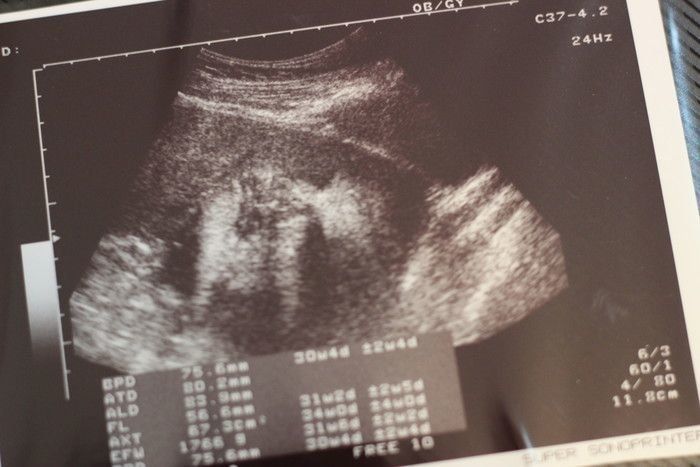

ママにエールさんの妊娠30週目のエコー写真

赤ちゃんは順調に成長して、推定体重1529g。気になっていた“逆子”の件は、無事に解決していました。妊婦検診までの期間ずっと、おなかの子に「頭を下にしてね~」と話していたのを、ちゃんと聞いてくれていたのかな…。などと思い、「お利口さん」とおなかをなでました。性別は謎のまま。「生まれてからのお楽しみ!」と、いたずら好きの赤ちゃんに言われているような気がしました。